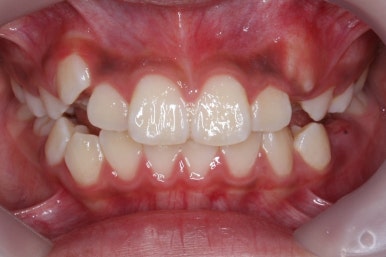

미소를 짓거나 웃는 모습이 확연히 좋아졌습니다.

덧니가 없어져서 그런지 입술 다문 모습도 편안함이 느껴지네요. 턱끝의 쭈글한 주름도 없어졌습니다.

헤드기어를 사용해서 옆모습의 돌출감도 개선이 되었고 무턱같아 보이던 외모도 많이 좋아졌네요.

이 정도면 비발치 연산동덧니교정으로도 충분히 좋았던 효과를 보았습니다.

연산동덧니교정을 하고자 키다리아저씨치과에 처음 내원했을 때와 개선이 된 후의 비교 모습입니다. 영구치가 모두 나왔고 덧니가 개선이 된 후에 마무리가 되었습니다.

처음에 언급했듯이 헤드기어에서 부터 장치부착까지 총 교정 기간은 1년 8개월이였습니ㅏㄷ.